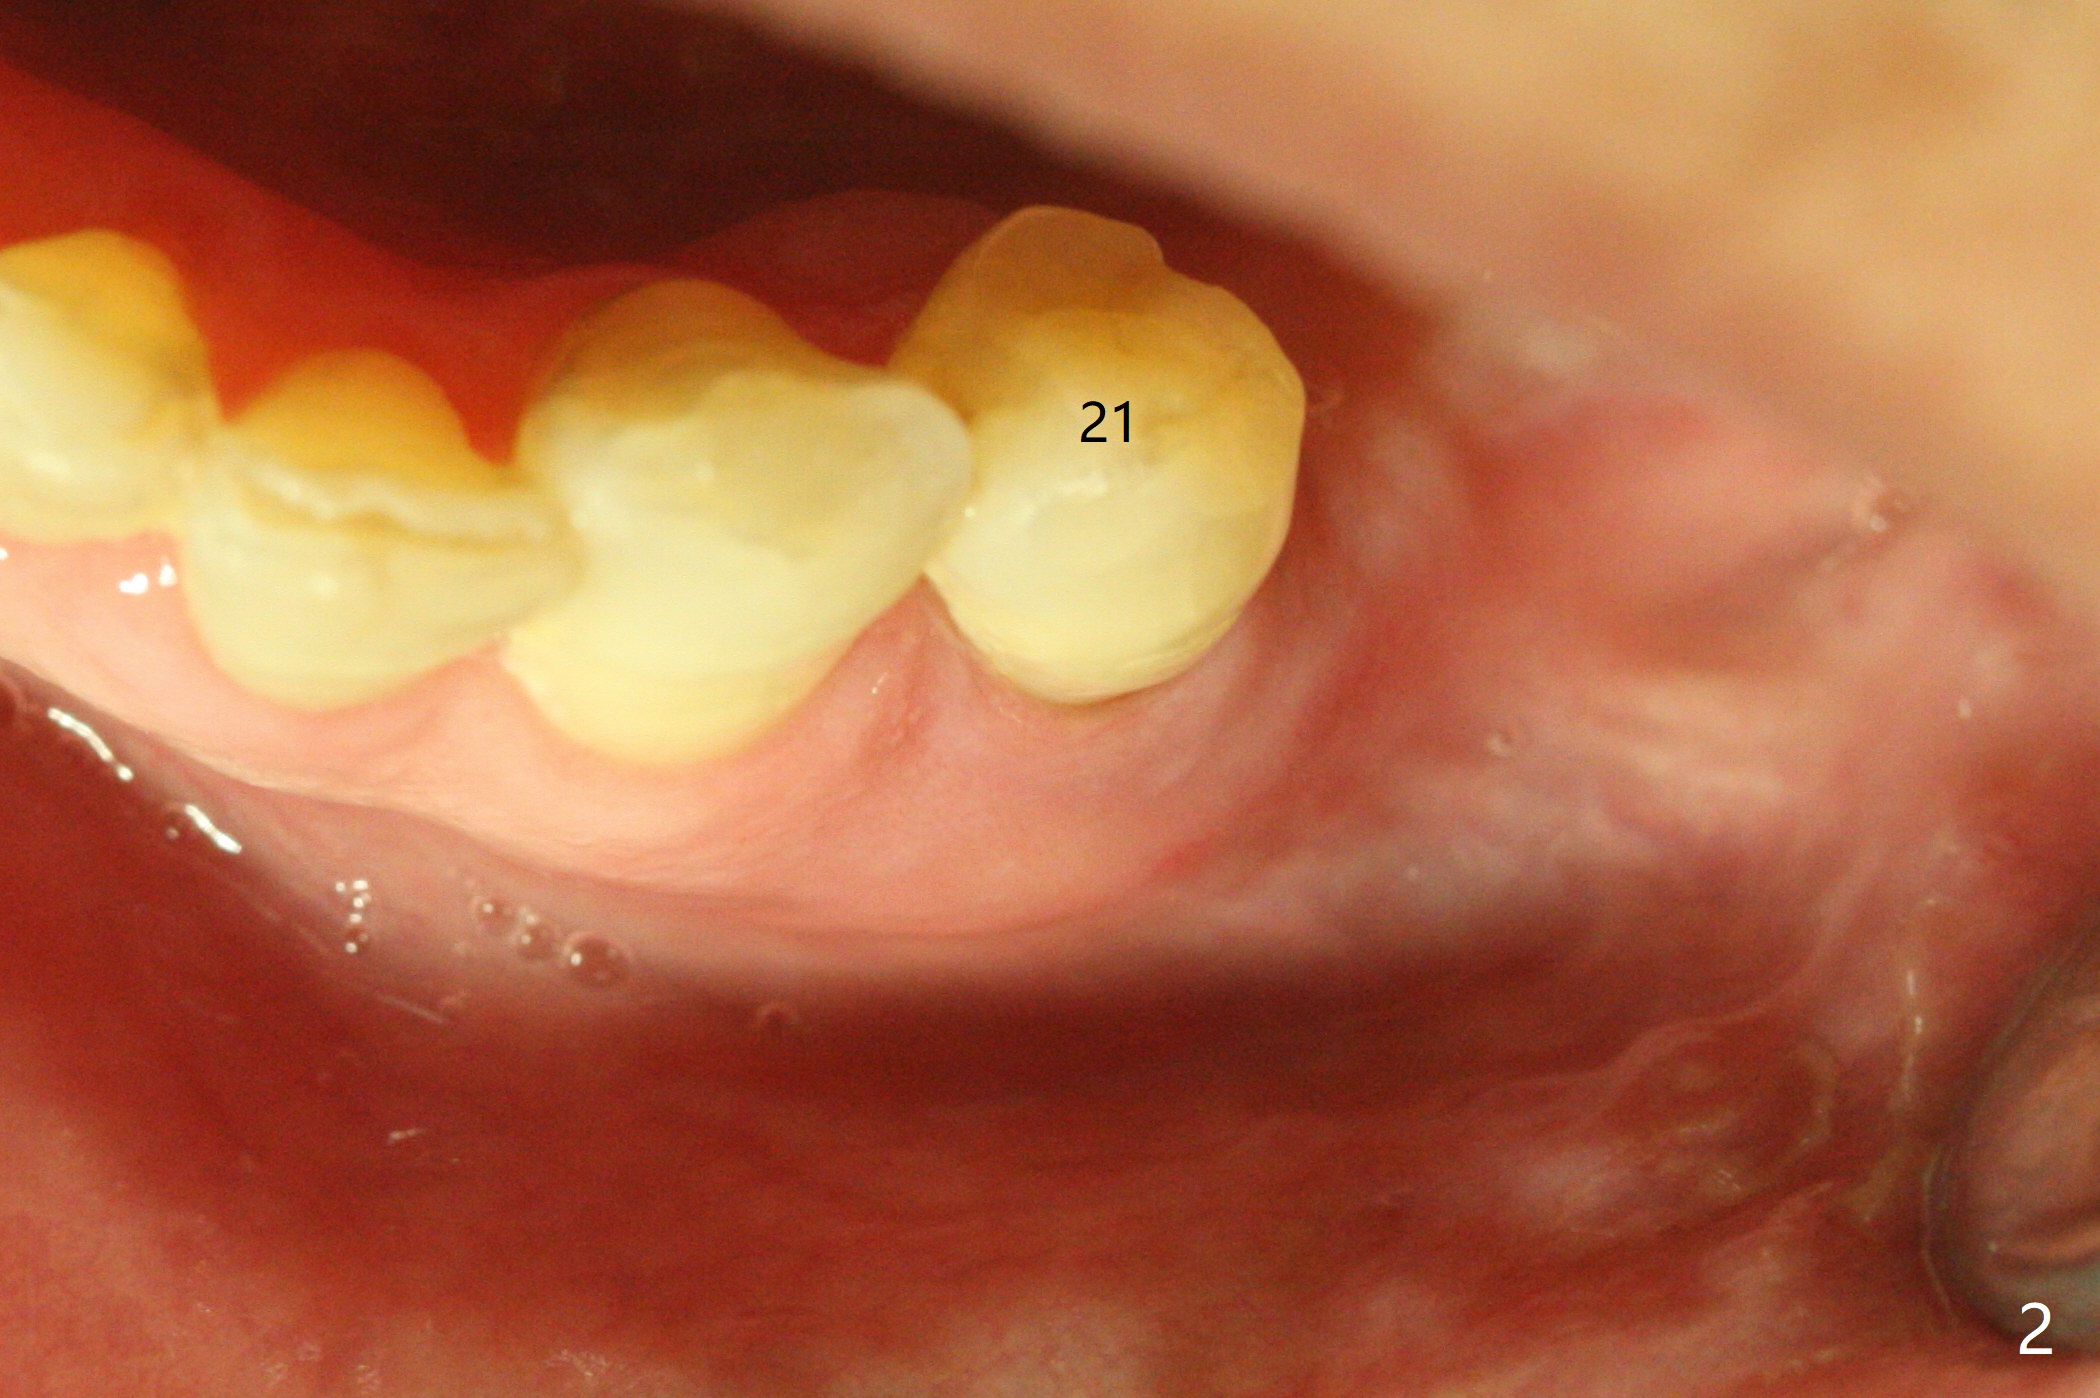

A 73-year-old man with history of stroke presented to office with #20 chewing pain 2 years ago (Fig.1). When he returns today, the tooth #20 has lost, while #21 has mobility (Fig.2), torus mandibularis (Fig.3 *) and severe bone loss, as related to Class V defect (Fig.4). As expected, the buccal plate is lost, the buccal gingiva blanching and bulging due to a curette underneath (Fig.5 *). After placement of allograft in the socket (Fig.6,8 *), a 8x8 mm BioXclude and 4-0 PGA suture are used to close the socket (Fig.7). Periodontal dressing stays in place 10 days postop (Fig.9). The patient is pleased with hemostasis. He is going to return his home state.